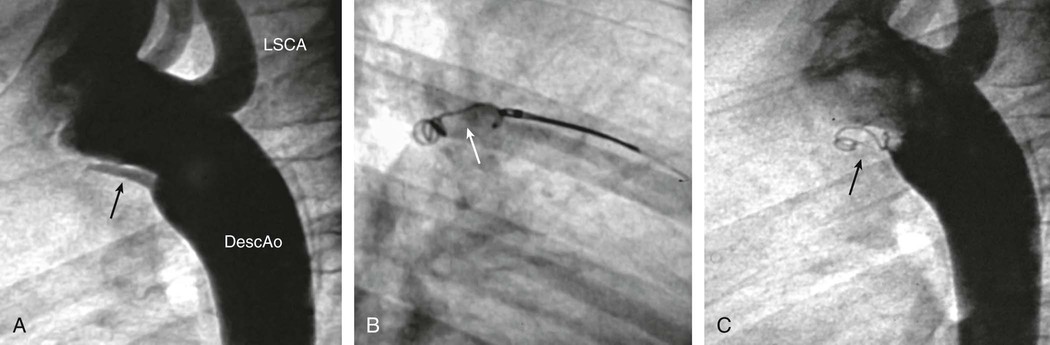

Transcatheter PDA closure is routinely performed in the cardiac catheterization laboratory (Fig. 426-11). Small PDAs are generally closed with intravascular coils. Moderate to large PDAs may be closed with an umbrella-like device or with a catheter-introduced sac into which several coils are released. Surgical closure of a PDA can be accomplished by a standard left thoracotomy or using thoracoscopic minimally invasive techniques. Because the case fatality rate with interventional or surgical treatment is considerably less than 1% and the risk without it is greater, closure of the ductus is indicated in asymptomatic patients, preferably before 1 yr of age. Pulmonary hypertension is not a contraindication to surgery at any age if it can be demonstrated at cardiac catheterization that the shunt flow is still predominantly left to right and that severe pulmonary vascular disease is not present. After closure, symptoms of cardiac failure rapidly disappear. Infants who had failed to thrive usually have immediate improvement in physical development. The pulse and blood pressure return to normal, and the machinery-like murmur disappears. A functional systolic murmur over the pulmonary area may persist; it may represent turbulence in a persistently dilated pulmonary artery. The radiographic signs of cardiac enlargement and pulmonary overcirculation disappear over a period of several months, and the electrocardiogram becomes normal.